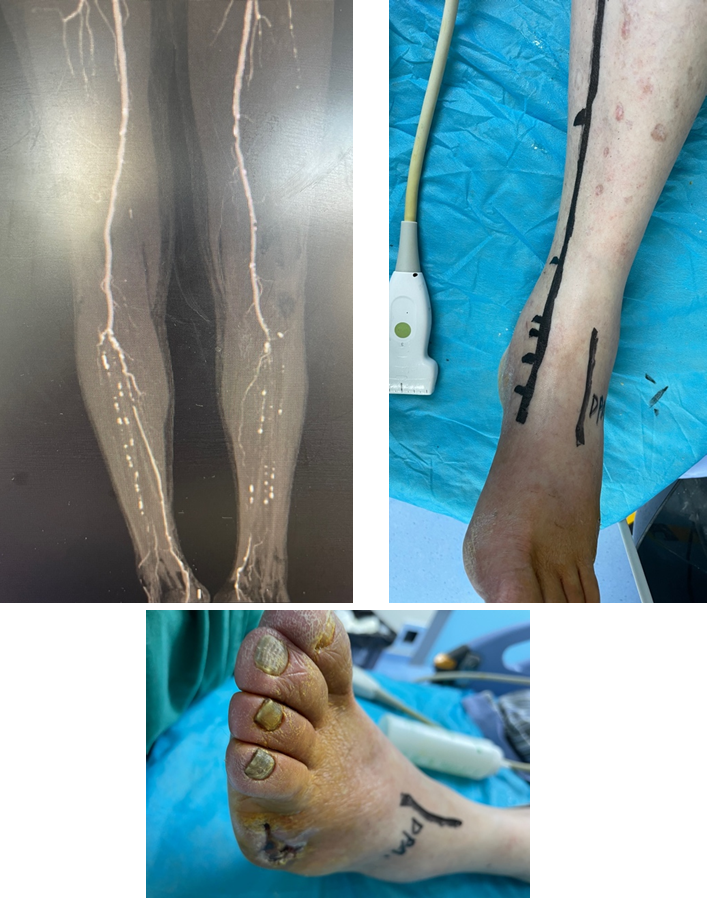

技术失败:R5 ischemia → 股总-远端胫后In-situ GSV旁路

4次EVTs反复复发:R5 ischemia → 腘P3-足背non-reversed GSV旁路

EVT后临床失败:R5 ischemia → 腘P3-足底动脉 reversed GSV旁路

307条肢体干预中,75例旁路手术经验:

两组中,均有高比例远端旁路(踝上及踝下):57% vs 47%

自体静脉使用率:85.34%